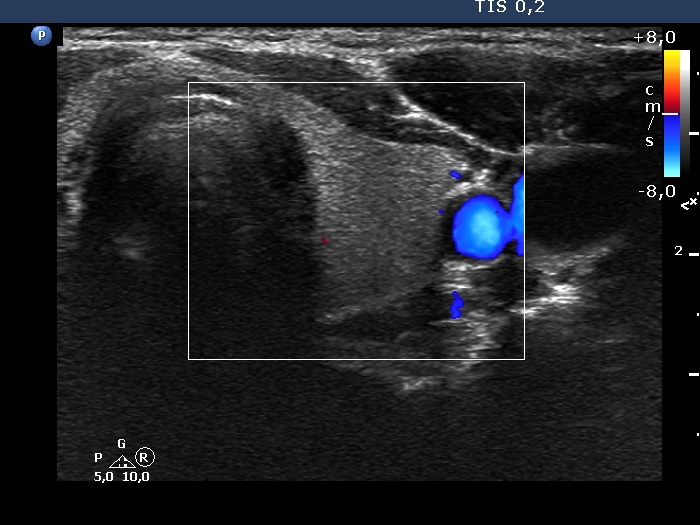

Left lobe, transverse scan, color Doppler mode. This lobe is almost avascular.